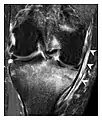

High-energy trauma fractures

Occult osseous injuries may result from a direct blow to the bone by compressive forces of adjacent bones against one another or by traction forces during an avulsion injury. Lesions in the tibial plateau, hip, ankle, and wrist are often missed. In a tibial plateau fracture, any disruption of the posterior and anterior cortical rims of the plateau should be sought. Impaction of subchondral bone will appear as an increased sclerosis of the subchondral bone (Figure 1). In the hip, posterior acetabular fractures also present subtle radiographic findings. The acetabular lines should then be carefully examined keeping in mind that the posterior rim, which is harder to see on X-rays, is more frequently fractured than the anterior rim (Figure 2). In the wrist, detection of carpal bone fractures is often challenging, with up to 18% of scaphoid fractures radiographically occult. Carpal fractures, especially the scaphoid, are associated with the risk of avascular necrosis. In apparently normal wrist radiographs from symptomatic patients, if there is history of a fall on an outstretched hand with pain in the anatomic snuffbox, suggesting scaphoid injury, the initial examination with posteroanterior, lateral, and pronation oblique views must be complemented by other specific views such as supination oblique and the "scaphoid" view A careful examination of cortices for evidence of discontinuity or offset and cancellous bone for lucency is necessary (Figure 3).[1]

a

b

c

Figure 1: A 56-year-old woman presenting with left knee pain after a fall. (a) Initial anteroposterior radiograph was considered normal, however, subtle cortical disruption of the anterior rim of the medial tibial plateau, medial to the tibial spine, is noted (arrow). (b) Coronal T1-weighted MRI confirms the cortical disruption (arrow) and shows extensive fracture through the proximal tibia. (c) Coronal proton density-weighted image with fat saturation shows extensive edema in the subchondral bone. Note also hypersignal adjacent to the medial collateral ligament corresponding to a grade I sprain (arrowheads).[1]